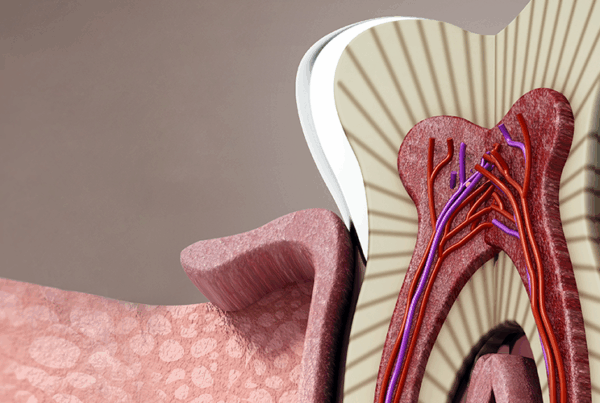

A tooth abscess is a pocket of pus caused by a bacterial infection. It forms in or around the tooth when bacteria invade the pulp, the innermost part of the tooth housing nerves and blood vessels. While the term “abscess” might sound alarming, what’s more concerning is leaving it untreated.

- Root Canal Therapy: If necessary, we’ll remove the infected pulp, clean the canal, and seal the tooth to prevent reinfection.